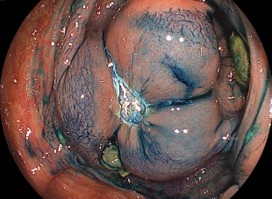

エンドカットモードで、短時間で切離することにより切除後潰瘍底に、凝固波による白濁が殆どありません。このように切離すると理論上の後出血のリスクは低くなります。

日帰り内視鏡切除の場合は、大型病変の切除後潰瘍底はclipで閉創します。